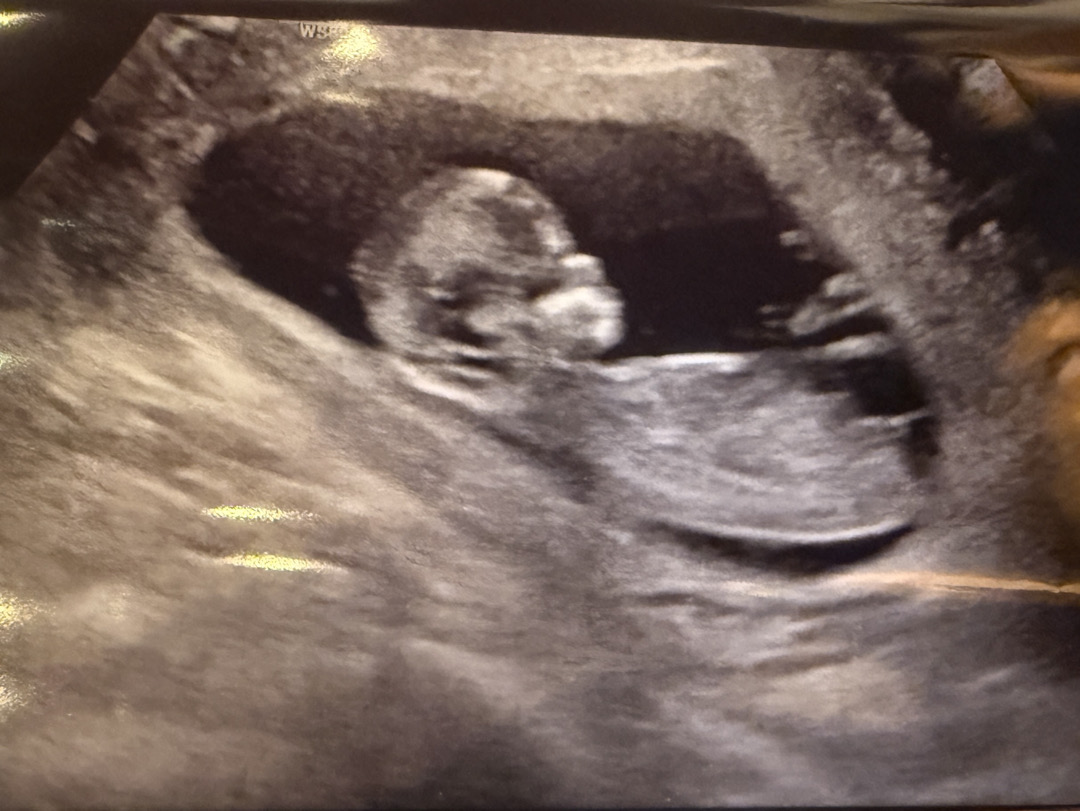

12주 4일차인데 성별 봐주세요!!

딸같아용